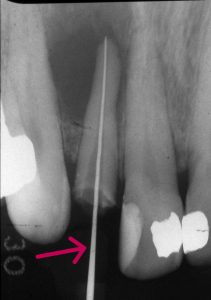

原因 根充剤のガッタパーチャポイントが根尖まで到達してしない。根尖に空間が出来ているので細菌感染を起こしている。

【根充剤が根尖まで全く到達していない】

【リーマーを根管内に挿入し歯根長を測定 根尖までリーマーが到達】